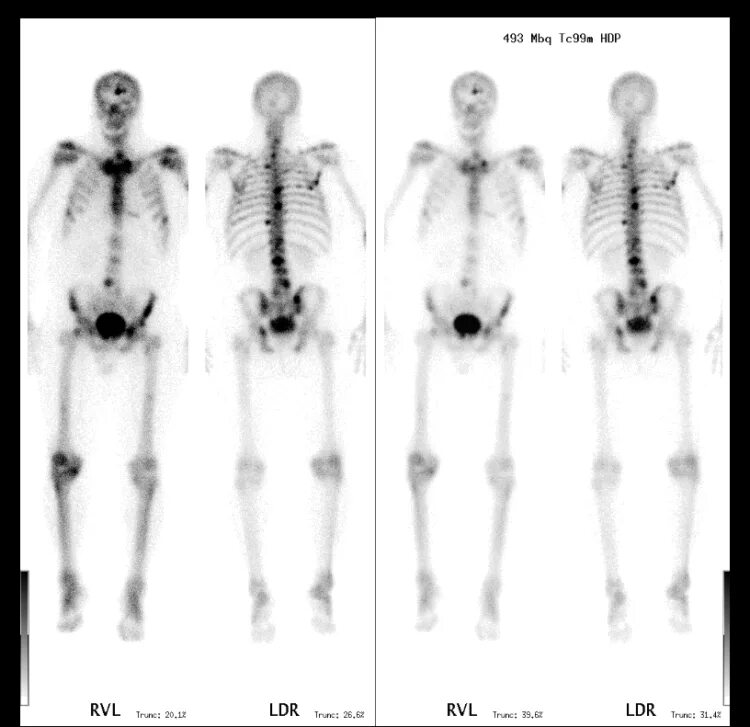

Метастазы скелета